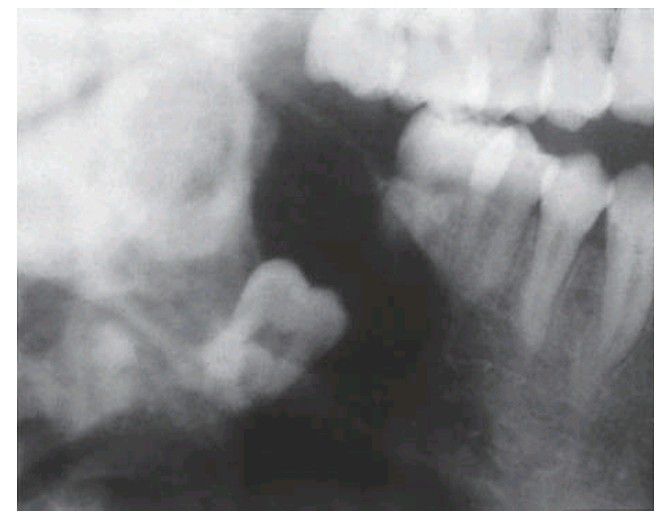

. This ameloblastoma forms a monolocular radiolucency enveloping the crown of an unerupted tooth. The radiological appearance mimics a dentigerous cyst, reinforcing the maxim that ameloblastoma should be considered in the differential diagnosis of every radiolucency at the angle of the mandible.